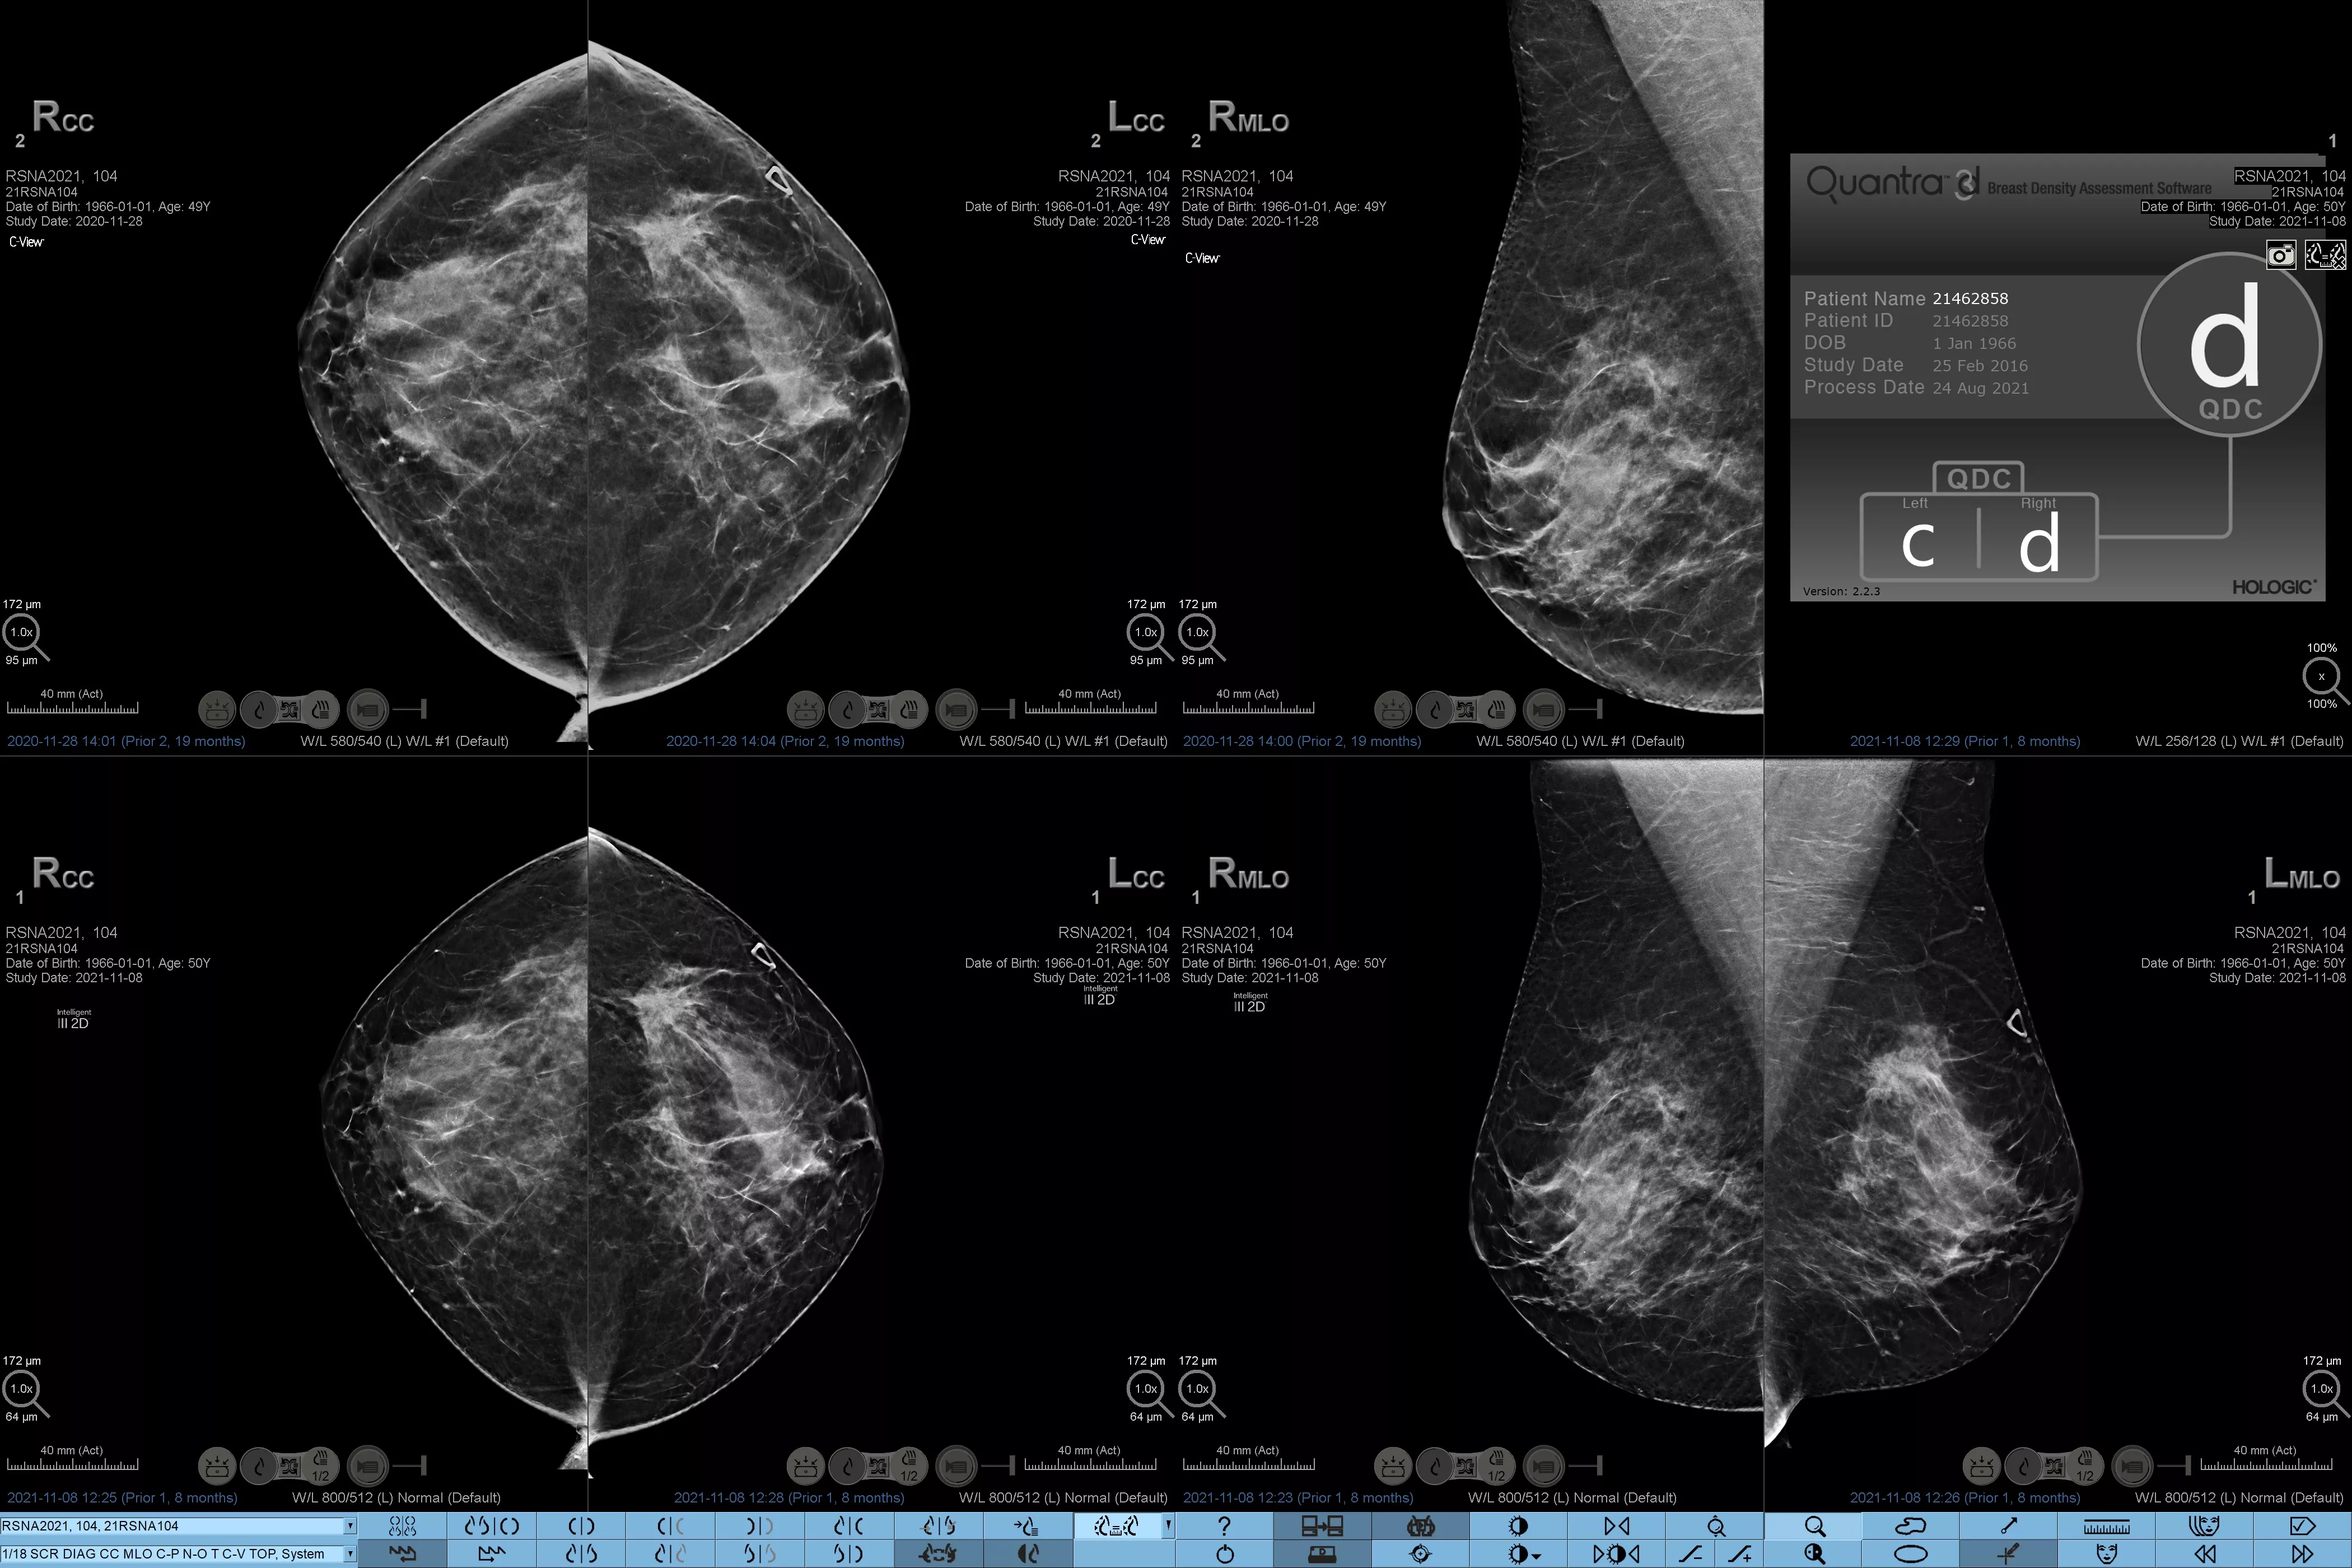

Higher breast density is known to increase a woman’s risk for breast cancer.1 The need for accurate, unbiased analysis is therefore critical. Powered by machine learning, Quantra technology software analyses both 2D™ and tomosynthesis images for distribution and texture of parenchymal tissue. It categorises breasts in four breast composition categories consistent with guidance from the American College of Radiology (ACR) BI-RADS Atlas 5th Edition.2

Objective machine learning algorithm that assigns breast density category based on analysis of breast tissue texture and patterns.

Quantra software’s unbiased algorithm analyse both 2D and tomosynthesis images to support your analysis by:

• Overcoming subjectivity in visual assessment, providing more consistent, and more reliable scoring.*

Breast imaging scans

*Scores are based on ACR BI-RADS categories, in line with the revised guidance by the American College of Radiation (ACR) BI-RADS Atlas 5th Edition. This accounts for pattern and texture, compared with volume, when determining density.